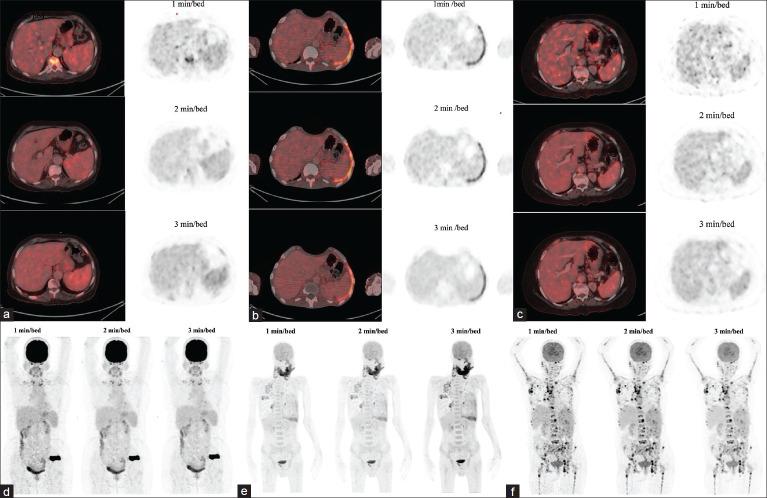

PET/CT scans were performed using GE's Discovery IQ 5-ring, 16-slice system within 40-60 minutes of intravenous F-FDG injection. The protocol was adjusted to a low-dose (0.05 mCi/kg of F-FDG), and the PET data acquisition time was increased to 3 min per bed position to ensure image quality.

Notable differences were observed in image quality scores based on varying acquisition times, with the extended acquisition time helping maintain diagnostic standards despite reduced tracer doses.

在静脉注射F-FDG后40 - 60分钟内,使用GE的Discovery IQ 5环16层系统进行PET/CT扫描。方案调整为低剂量(0.05 mCi/kg的F-FDG),并且PET数据采集时间增加到每个床位位置3分钟以确保图像质量。

基于不同采集时间观察到图像质量评分存在显著差异,尽管示踪剂剂量减少,但延长的采集时间有助于维持诊断标准。